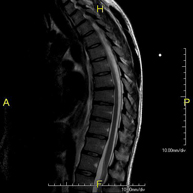

- Lumbar spine MRI

This non-invasive diagnostic procedure uses an electromagnetic field and radio waves (from a transmitter and receiver) to acquire high-definition anatomical images of the lumbar and sacral regions. It is a radiation-free procedure. Indicated for: trauma, sciatica, herniated discs, tumours, infections.